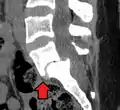

Anterolisthesis L5/S1

Anterolisthesis L5/S1. Blue arrow normal pars interarticularis. Red arrow is a break in pars interarticularis.